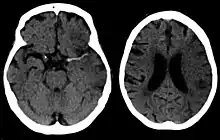

Silent stroke

Silent stroke is stroke that does not have any outward symptoms, and people are typically unaware they had experienced stroke. Despite not causing identifiable symptoms, silent stroke still damages the brain and places the person at increased risk for both transient ischemic attack and major stroke in the future. Conversely, those who have had major stroke are also at risk of having silent stroke.[54] In a broad study in 1998, more than 11 million people were estimated to have experienced stroke in the United States. Approximately 770,000 of these were symptomatic and 11 million were first-ever silent MRI infarcts or hemorrhages. Silent stroke typically causes lesions which are detected via the use of neuroimaging such as MRI. Silent stroke is estimated to occur at five times the rate of symptomatic stroke.[55][56] The risk of silent stroke increases with age, but they may also affect younger adults and children, especially those with acute anemia.[55][57]

Stroke is diagnosed through several techniques: a neurological examination (such as the NIHSS), CT scans (most often without contrast enhancements) or MRI scans, Doppler ultrasound, and arteriography. The diagnosis of stroke itself is clinical, with assistance from the imaging techniques. Imaging techniques also assist in determining the subtypes and cause of stroke. There is yet no commonly used blood test for the stroke diagnosis itself, though blood tests may be of help in finding out the likely cause of stroke.[68] In deceased people, an autopsy of stroke may help establishing the time between stroke onset and death.

Imaging

- MRI scan

- sensitivity= 83%

- specificity= 98%

For detecting chronic hemorrhages, an MRI scan is more sensitive.[70]

CT scans may not detect ischemic stroke, especially if it is small, of recent onset,[10] or in the brainstem or cerebellum areas (posterior circulation infarct). MRI is better at detecting a posterior circulation infarct with diffusion-weighted imaging.[71] A CT scan is used more to rule out certain stroke mimics and detect bleeding.[10] The presence of leptomeningeal collateral circulation in the brain is associated with better clinical outcomes after recanalization treatment.[72] Cerebrovascular reserve capacity is another factor that affects stroke outcome – it is the amount of increase in cerebral blood flow after a purposeful stimulation of blood flow by the physician, such as by giving inhaled carbon dioxide or intravenous acetazolamide. The increase in blood flow can be measured by PET scan or transcranial doppler sonography.[73] However, in people with obstruction of the internal carotid artery of one side, the presence of leptomeningeal collateral circulation is associated with reduced cerebral reserve capacity.[74]